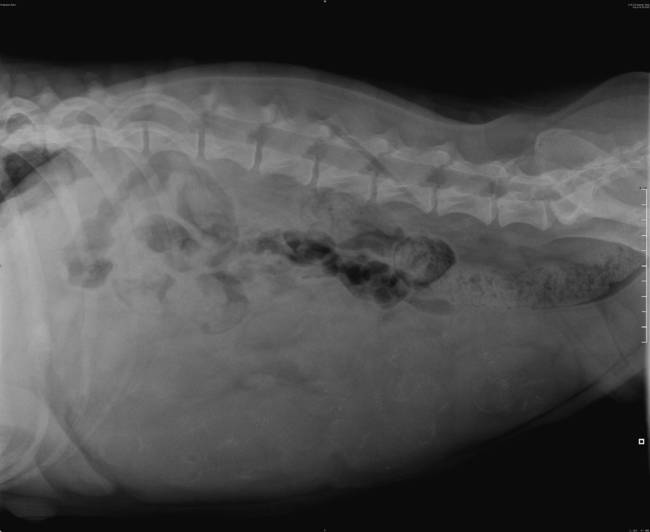

vraagje aan de fokkers onder ons of aan die gene die heel goed rontgen kunnen bekijken dit is een rx gemaakt op de 49 ste dag ven de dracht bij een bordeauxdog ik kan 14 pups tellen maar vind de foto onduidelijk

ik heb het geplaatst omdat ik een werkstuk moet maken ik ben bezig met een opleiding voor dierenarts assistente en er is mijn gevraagd om deze foto te bekijken en te oordelen omdat het dus steeds vaker voor komt dat de rx te onduidelijk zijn deze teef dracht ook veel vruchtwater bij zich ik hoop zo dat ik de informatie goed heb neergezet.gr cornelia

het is heel slecht te zien maar als je de foto vergroot zie je het iets beter maar dan nog moet je heel goed kijken.

we kregen het op mijn foto ook niet getelt, niemand en ik vond mijn foto duidelijker.

dierenarts zei tussen 9 a 12 en er zijn er 10 geboren.